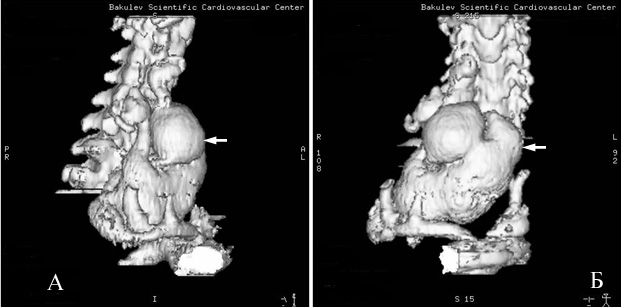

Рис.4 Трехмерная реконструкция (SSD) аневризмы правой позвоночной артерии.

А- боковая проекция.

Б- прямая проекция.

Спиральная компьютерная томография брахиоцефальных артерий с внутривенным болюсным введением Омнипака 300- 80,0: Грудная аорта без видимой патологии, обычного диаметра, левые общая сонная и подключичная артерии расположены типично. Брахиоцефальный ствол смещен кпереди и вправо. Правая общая сонная артерия диаметром 7 мм, правая подключичная артерия в устье имеет диаметр10 мм. От нее отходит правая позвоночная артерия диаметром 10 мм (рис 1).

Правая позвоночная артерия после отхождения от подключичной артерии отклонена несколько вправо, идет назад, делая S-образный изгиб загрудинно резко неравномерно расширяется до 25 мм, далее расширенная артерия «делает» петлю, образуя мешковидное сосудистое образование распространяется вниз в грудную клетку до правой ветви легочной артерии, вверх до С5, размерами 87×40 мм. После образования петли позвоночная артерия по передней поверхности тела позвонка сужается до 10 мм, идет косо вниз и вправо, затем снова расширяется до 27 мм и на уровне С6 входит в позвоночный спинномозговой канал (рис.1,4). Дистальнее правая позвоночная артерия расширена и извита, в позвоночном канале соединяется с резко расширенными корешковыми ветвями и также резко расширенной правой спинальной артерией (спинной мозг оттеснен влево и кзади) (рис.3). Отмечается выраженная деформация поперечного отростка С6 справа, обусловленная длительной компрессией расширенными сосудами.